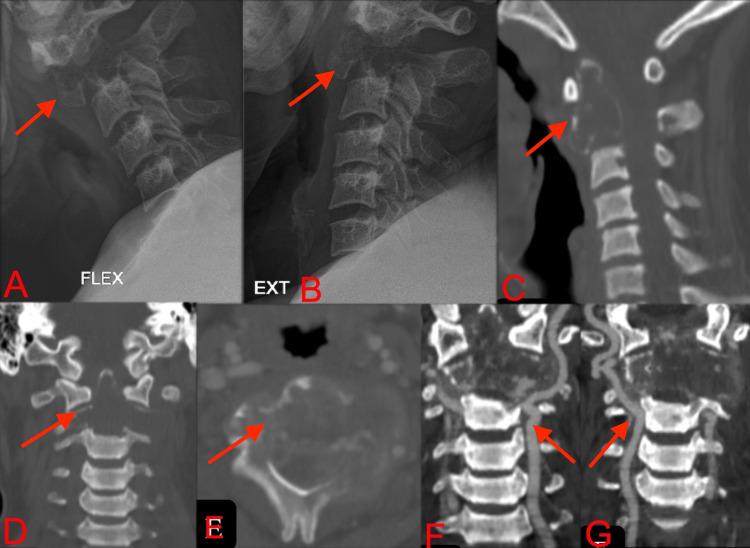

A 25-year-old man presented with symptoms of cervical myelopathy for 10 days. Imaging revealed an expansile, lytic lesion involving the C2 vertebra completely and compressing the spinal cord, suggestive of giant cell tumor (GCT). Tumor resection and posterior stabilization from C1-C4 were done. Histopathology confirmed the diagnosis of GCT. The patient was kept on adjuvant Denosumab (D-ab) for two years with no signs of recurrence. However, discontinuation of D-ab therapy led to recurrence of the tumor within three months, which was managed with repeated surgical resection and anterior instrumentation followed by radiotherapy. To the best of our knowledge, this is the first reported case of GCT involving the upper cervical spine with rapid recurrence following the stoppage of D-ab therapy.

一名25岁男性出现颈髓病症状10天。影像学检查显示一个膨胀性溶骨性病变,完全累及C2椎体并压迫脊髓,提示为骨巨细胞瘤(GCT)。进行了肿瘤切除及C1 - C4后路固定术。组织病理学确诊为GCT。患者接受辅助地诺单抗(D - ab)治疗两年,无复发迹象。然而,停用D - ab治疗后三个月内肿瘤复发,通过再次手术切除及前路内固定,随后进行放疗进行处理。据我们所知,这是首例报道的累及上颈椎的GCT在停用D - ab治疗后快速复发的病例。